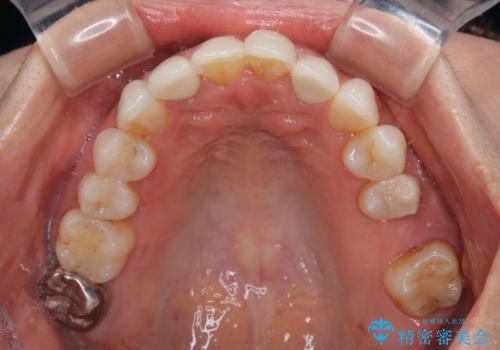

前歯のデコボコとむし歯治療の跡 インビザライン矯正とオールセラミッククラウン治療

- 前歯のセラミッククラウンの縁が見えることが気になってから、デコボコも気になるようになってきたとのことで来院された患者様です。

デコボコの程度は中等度であったため、インビザライン・モデレートパッケージにて歯列を整えることとしました。

セラミッククラウンの装着されていた前歯と、大きな修復治療の跡がある反対側の歯は、矯正治療後に補綴治療を行うこととしました。